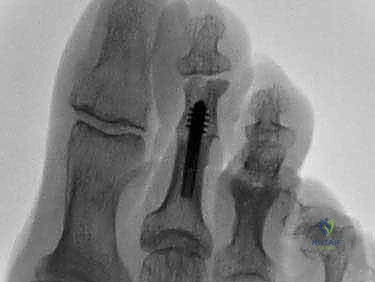

ب. تثبيت المفصل (Arthrodesis - Joint Fusion)

يُعتبر هذا الإجراء المعيار الذهبي لحالات إصبع القدم المطرقية الصلب جداً والمؤلم، أو الحالات المرتجعة. يقوم الدكتور هطيف بإزالة الغضروف التالف من نهايتي العظمتين المكونتين للمفصل الأوسط (PIP)، ثم يتم دمج العظمتين معاً لتكوين عظمة واحدة صلبة ومستقيمة.

* الميزة: يوفر استقامة دائمة وقوية للإصبع، ويقضي على الألم تماماً لأنه يمنع أي حركة في المفصل التالف.

* طرق التثبيت: تقليدياً، تُستخدم أسلاك كيرشنر (K-wires) التي تبرز من طرف الإصبع وتُزال بعد عدة أسابيع. ولكن، مع التقدم التكنولوجي، يستخدم الدكتور هطيف في كثير من الأحيان غرسات داخلية حديثة (Intramedullary Implants) أو براغي دقيقة جداً تبقى داخل العظم، مما يجنب المريض إزعاج الأسلاك الخارجية ويسرع من عملية التأهيل.

توضيح لعملية تثبيت المفصل Arthrodesis باستخدام الغرسات الحديثة